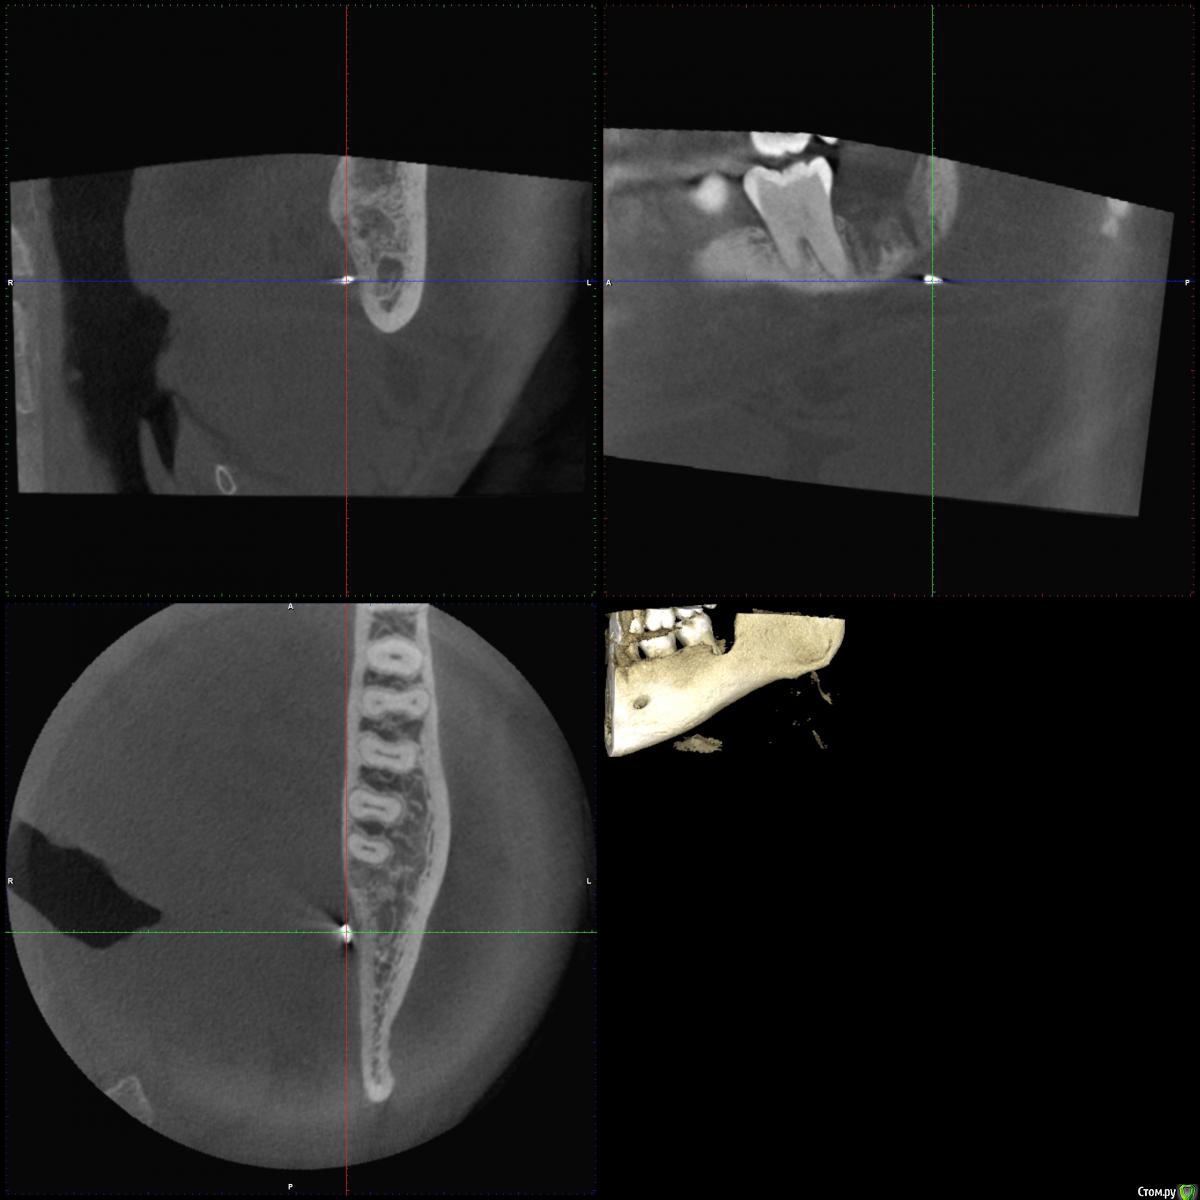

medbratec Опубликовано 9 октября, 2016 Поделиться Опубликовано 9 октября, 2016 (изменено) Предыстория:к 30 годам вылезла наконец часть 38-го. Пару лет с переменным успехом я боролся с воспалением капюшона (перикоронит как я понял называется) без помощи специалистов. Наконец решил избавиться от него радикально - удалением зуба.Зуб обломали, после пытались остатки вытащить в течении 3 часов, шатали/стучали и прочее, пока я сам не прервал экзекуцию. Затем направление в челюстно-лицевую, бормашина и т.д. И так, 20 июля проведена операция после неполного удаления 38 зуба. Через неделю был выписан. Еще через 2 недели обратился повторно с жалобами на не проходящую припухлость, сочение из лунки сукровицы и периодическую ноющую боль. Был проведен осмотр с применением инструментов и анестезии, достали осколок, сказали что воспаления надкостницы нет, назначили УВЧ. Провел физиопроцедуру в количестве 15шт. Стало лучше, даже начал жевать на обе стороны, чувство дискомфорта уменьшилось, реакция на горячее/холодное уменьшилась.В конце сентября загриповал и все симптомы обострились снова. На днях посетил специалиста, сделал снимок(прикреплен).Описание : На Р-грамме левой ветви нижней челюсти в косой проекции замыкательные пластины нижней челюсти не изменены. В толще тела определяется плотное инородное тело 0.3*0.1см.Специалист изучив снимок сказал, что по всей видимости в воспалительный процесс вовлечен соседний с удаленным зубом. Предлагает депульпировать 7-мерку, а затем провести операцию по костной пластике для заполнения полости от 8-ки, и добавив тем самым опору для 7-ки, попутно попытаться достать осколок косточки(инородное тело).В этот же день я был еще в одной клинике, где мне так же предложили 7-ку депульпировать для начала, а про инородное тело сказали, что это скорее всего обломан инструмент, предположительно зонд и стоит 10 раз подумать доставать ли его. Симптоматика на сегодняшний день:со стороны удаления воспалена миндалина, причем воспаление после выпиливания, а это уже более 2-ух месяцев, так полностью и не проходило. Увеличены лимфоузлы возле скулы и уха. Глотаю без болей.Болезненная реакция на горячее/холодное не только 7-ки, но и 3,4 зуба(сразу оговорюсь они раньше не реагировали да и внешне здоровы). При постукивании металлом 7-ка наиболее болезненна. Так же у 7-го боль при сильном нажиме, жевании сухарей например. Еще 7-ой стал заметно качаться. Чистка зубов неприятных ощущений не вызывает. На кислое, сладкое и прочие раздражители реакция слабая.Внешне в районе скулы есть еле заметная припухлость. При пальпации в месте удаления незначительные болевые ощущения.Испытываю скорее дискомфорт, чем боль при открытии рта и улыбке. Из лунки сочиться сукровица и видны кусочки тканей (возможно выгнивающей). На внешней стороне лунки наблюдается что-то похожее на флюс(надувется/здувается в течении дня, а также изменяет свой объем и плотность во время пальпации щеки снаружи).Головные боли, небольшая температура преимущественно в первой половине дня, нарушение сна, слабость. Я не медик, однако озвучу свои мысли по поводу лечения - вскрыть предполагаемый флюс, провести дезинфекцию, наложить швы, оставить дренаж на некоторое время. Параллельно антибиотикотерапия и электрофорез челюсти. Если все наладиться, то провести костную пластику с целью укрепления "посадочного места" 7-ки и скрытия его корней со стороны лунки. В данный момент я в растерянности. Хотел бы услышать мнение по поводу инородного тела - это осколок кости или обломок инструмента, что с этим делать, нужно ли его доставать, может ли он являться причиной воспаления, а не 7-мой зуб ?Очень не хочется напрасно омертвлять 7-ку. Какую стратегию лечения можете посоветовать ? п.с. постараюсь к вечеру сделать фото места удаления зуба. Изменено 9 октября, 2016 пользователем medbratec Ссылка на комментарий

Kazankov.Egor Опубликовано 9 октября, 2016 Поделиться Опубликовано 9 октября, 2016 Предыстория:к 30 годам вылезла наконец часть 38-го. Пару лет с переменным успехом я боролся с воспалением капюшона (перикоронит как я понял называется) без помощи специалистов. Наконец решил избавиться от него радикально - удалением зуба.Зуб обломали, после пытались остатки вытащить в течении 3 часов, шатали/стучали и прочее, пока я сам не прервал экзекуцию. Затем направление в челюстно-лицевую, бормашина и т.д. И так, 20 июля проведена операция после неполного удаления 38 зуба. Через неделю был выписан. Еще через 2 недели обратился повторно с жалобами на не проходящую припухлость, сочение из лунки сукровицы и периодическую ноющую боль. Был проведен осмотр с применением инструментов и анестезии, достали осколок, сказали что воспаления надкостницы нет, назначили УВЧ. Провел физиопроцедуру в количестве 15шт. Стало лучше, даже начал жевать на обе стороны, чувство дискомфорта уменьшилось, реакция на горячее/холодное уменьшилась.В конце сентября загриповал и все симптомы обострились снова. На днях посетил специалиста, сделал снимок(прикреплен).Описание : На Р-грамме левой ветви нижней челюсти в косой проекции замыкательные пластины нижней челюсти не изменены. В толще тела определяется плотное инородное тело 0.3*0.1см.Специалист изучив снимок сказал, что по всей видимости в воспалительный процесс вовлечен соседний с удаленным зубом. Предлагает депульпировать 7-мерку, а затем провести операцию по костной пластике для заполнения полости от 8-ки, и добавив тем самым опору для 7-ки, попутно попытаться достать осколок косточки(инородное тело).В этот же день я был еще в одной клинике, где мне так же предложили 7-ку депульпировать для начала, а про инородное тело сказали, что это скорее всего обломан инструмент, предположительно зонд и стоит 10 раз подумать доставать ли его. Симптоматика на сегодняшний день:со стороны удаления воспалена миндалина, причем воспаление после выпиливания, а это уже более 2-ух месяцев, так полностью и не проходило. Увеличены лимфоузлы возле скулы и уха. Глотаю без болей.Болезненная реакция на горячее/холодное не только 7-ки, но и 3,4 зуба(сразу оговорюсь они раньше не реагировали да и внешне здоровы). При постукивании металлом 7-ка наиболее болезненна. Так же у 7-го боль при сильном нажиме, жевании сухарей например. Еще 7-ой стал заметно качаться. Чистка зубов неприятных ощущений не вызывает. На кислое, сладкое и прочие раздражители реакция слабая.Внешне в районе скулы есть еле заметная припухлость. При пальпации в месте удаления незначительные болевые ощущения.Испытываю скорее дискомфорт, чем боль при открытии рта и улыбке. Из лунки сочиться сукровица и видны кусочки тканей (возможно выгнивающей). На внешней стороне лунки наблюдается что-то похожее на флюс(надувется/здувается в течении дня, а также изменяет свой объем и плотность во время пальпации щеки снаружи).Головные боли, небольшая температура преимущественно в первой половине дня, нарушение сна, слабость. Я не медик, однако озвучу свои мысли по поводу лечения - вскрыть предполагаемый флюс, провести дезинфекцию, наложить швы, оставить дренаж на некоторое время. Параллельно антибиотикотерапия и электрофорез челюсти. Если все наладиться, то провести костную пластику с целью укрепления "посадочного места" 7-ки и скрытия его корней со стороны лунки. В данный момент я в растерянности. Хотел бы услышать мнение по поводу инородного тела - это осколок кости или обломок инструмента, что с этим делать, нужно ли его доставать, может ли он являться причиной воспаления, а не 7-мой зуб ?Очень не хочется напрасно омертвлять 7-ку. Какую стратегию лечения можете посоветовать ? п.с. постараюсь к вечеру сделать фото места удаления зуба.Инородное тело металлической плотности, скорее всего инструмент, удаление его является приоритетом при наличии жалоб, а таковые имеют место быть. Ссылка на комментарий

kriokov Опубликовано 10 октября, 2016 Поделиться Опубликовано 10 октября, 2016 обратиться еще раз к специалисту, думаю надо - выполнить клкт или оптг-- проверить на витальность шестой и седьмой зубы-- осмотр личнопо результату принимать решение, нужна ревизия или нет. Инородное тело на рентгенограмме по плотности металл, и вряд ли дает ту симптоматику которую Вы описываете. 1 Ссылка на комментарий

kriokov Опубликовано 10 октября, 2016 Поделиться Опубликовано 10 октября, 2016 на оптг следы контраста от йодоформного тампона, не видно четко кортикальную, да и время прошло. Лучше клкт. Крымских стоматологов не знаю к сожалению 1 Ссылка на комментарий

medbratec Опубликовано 12 октября, 2016 Автор Поделиться Опубликовано 12 октября, 2016 Был на консультации в частной клинике.Вердикт - семерку лучше пока не трогать, ее чувствительность обусловлена оголенными корнями. Проводить ревизию лунки, доставать осколок вежливо отказались, и отправляют с этим в челюстно-лицевую.Посоветовали сделать клкт для прояснения картины. Я сделал, однако повторную консультацию пришлось отложить. Не знаю как оттуда вытащить картинки. Если кому будет не лень, то оставлю ссылку на скачивание образа диска. (600мб)Рентгенолог сказал, что осколок в мягких тканях, причем с внутренней стороны, также обнаружилась кариозная полость в месте соприкосновения 7-го и 6-го зуба. Ссылка на комментарий

medbratec Опубликовано 13 октября, 2016 Автор Поделиться Опубликовано 13 октября, 2016 Я вас прекрасно понимаю. Был бы специалистом, то так сразу и сделал. Просто не знаю, что конкретно и под каким углом показывать. Сделал несколько скриншотов. Напишите, если они окажутся не слишком информативны. Ссылка на комментарий

medbratec Опубликовано 13 октября, 2016 Автор Поделиться Опубликовано 13 октября, 2016 Ссылка на комментарий

IvanK Опубликовано 14 октября, 2016 Поделиться Опубликовано 14 октября, 2016 скорее всего , это пломбировочный материал, лежит он не в костной ткани, а в мягких тканях, если не беспокоит, то можно не трогать 1 Ссылка на комментарий

red_butler Опубликовано 17 октября, 2016 Поделиться Опубликовано 17 октября, 2016 если это пломбировочный материал то на снимках "до" он должен быть, но я вижу там что то металлическое 2 Ссылка на комментарий

kramer Опубликовано 22 октября, 2016 Поделиться Опубликовано 22 октября, 2016 если это пломбировочный материал то на снимках "до" он должен быть, но я вижу там что то металлическоеЧисто по снимку похоже на кончик твердосплавного бора. ИМХО. Ссылка на комментарий